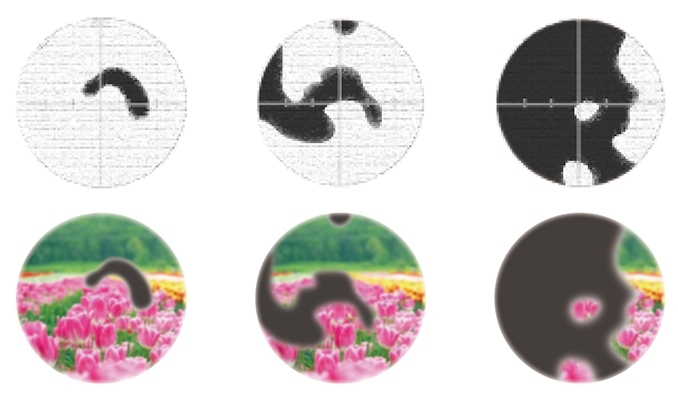

緑内障の症状

視神経が圧迫され、視野(見える範囲)が狭くなっていく疾患を緑内障と言います。視神経は、眼で見た情報を脳に伝える大事や役割をしています。網膜で感じた光を脳で認識できるのも、視神経があるからです。視神経は、120万本ほどの神経線維の束となっていますが、それも加齢とともに少しずつ減少していきます。この視神経は、通常ゆっくり減少するため視野が欠けることはありませんが、緑内障の患者様においては減少スピードが速く、視野が欠けていくという症状をもたらします。

初期症状は、両目もしくは片目に暗点(見えない点)ができます。この初期の段階では見えている(問題のない)側で補うために、なかなか見えにくいと自覚することはありません。しかし、徐々に暗点が広がり、日常生活にも支障を及ぼし、さらに悪化すると失明の恐れがあります。ゆっくり進行するため、気付いたときには病状がかなり進行しているケースが多く見られます。